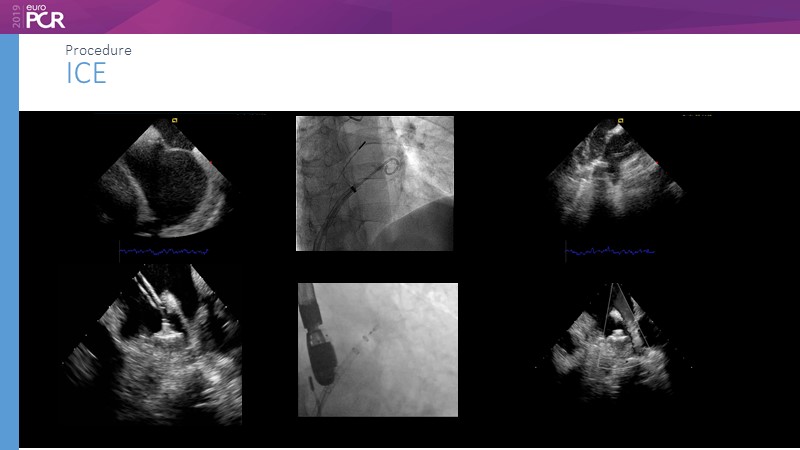

I. Cruz-Gonzalez

Pre-procedure planning

M. Sandri

Optimising procedural outcome and safety